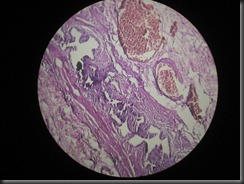

BPH-benign prostatic hyperplasia High Resolution Histology Slide

BPH  high resolution histology slide tsnaps

BPH –benign prostatic hyperplasia

High Resolution Histology Slide © Tsnaps

Click on the image to enlarge it , you may need to save the image to computer to view it in full zoom once its opened by clicking .

Since it’s a high resolution image ,opening of the image may take time.

Feel Free to use images for educational purposes.

Share us on Facebook if you like our work.